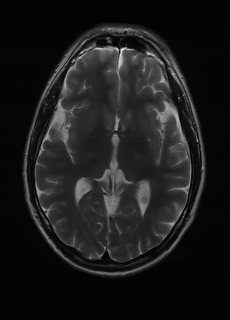

Sequence LR SISO MIMO MIMO tuned GT

λT1=2.90subscript𝜆subscript𝑇12.90\lambda_{T_{1}}=2.90 Refer to caption (a) 38.30/0.9484 Refer to caption (b) 45.03/0.9920 Refer to caption (c) 45.35/0.9926 Refer to caption (d) 46.70/0.9951 Refer to caption (e) PSNR/SSIM

λT2=2.44subscript𝜆subscript𝑇22.44\lambda_{T_{2}}=2.44 Refer to caption (f) 29.78/0.8990 Refer to caption (g) 35.43/0.9720 Refer to caption (h) 35.93/0.9752 Refer to caption (i) 37.05/0.9809 Refer to caption (j) PSNR/SSIM

λflair=7.82subscript𝜆𝑓𝑙𝑎𝑖𝑟7.82\lambda_{flair}=7.82 Refer to caption (k) 41.24/0.9412 Refer to caption (l) 44.54/0.9850 Refer to caption (m) 45.66/0.9885 Refer to caption (n) 46.15/0.9891 Refer to caption (o) PSNR/SSIM

Figure 5: Visual comparison of different recovery methods on real data